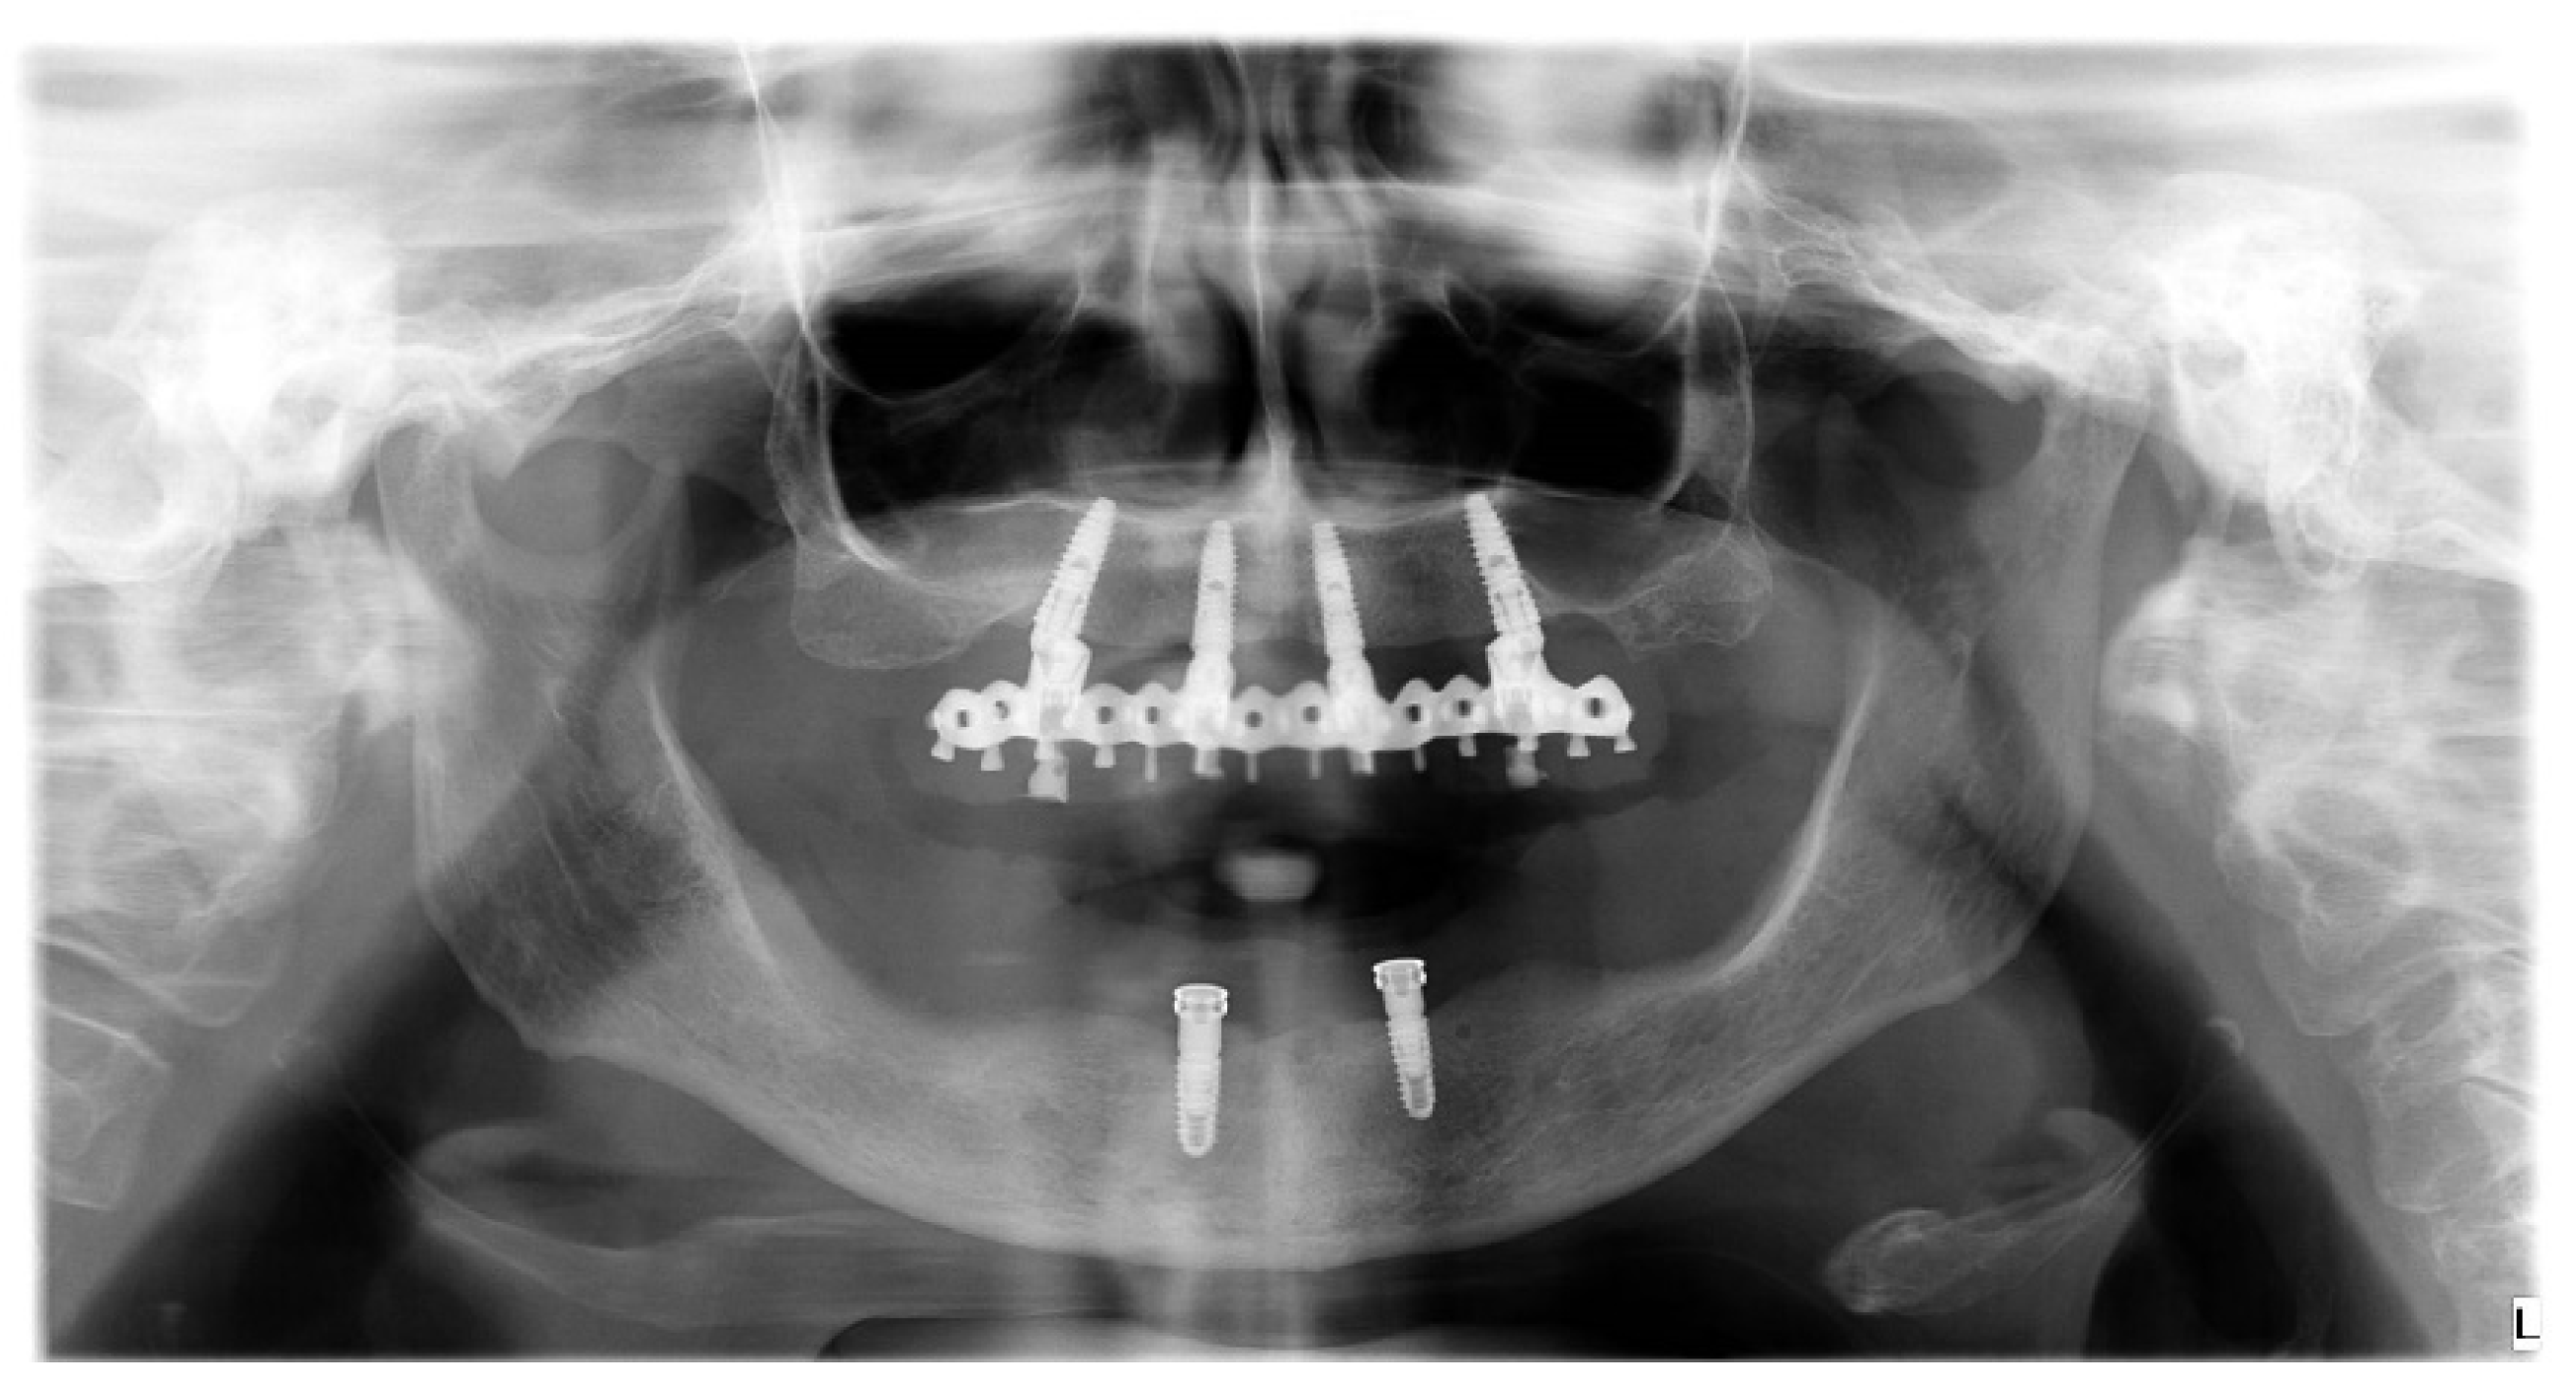

- Accuracy was tested by means of direct vision and tactile sensation, performed by applying alternately pressure on the aluminum try-in, and then the definitive metal framework (Alternate Pressure Technique), secured without screws, to determine if any movement occurs. In addition, the one-screw test proposed by Jemt and co-workers was performed in case of doubts occurred [11]. No discrepancy of the radiopaque, aluminum try-in, secured with only one screw tightened, was observed [11]. Peri-apical radiographs were taken if needed. The same operator (MT) performed both tests using a microscope magnification (10× to 16×);